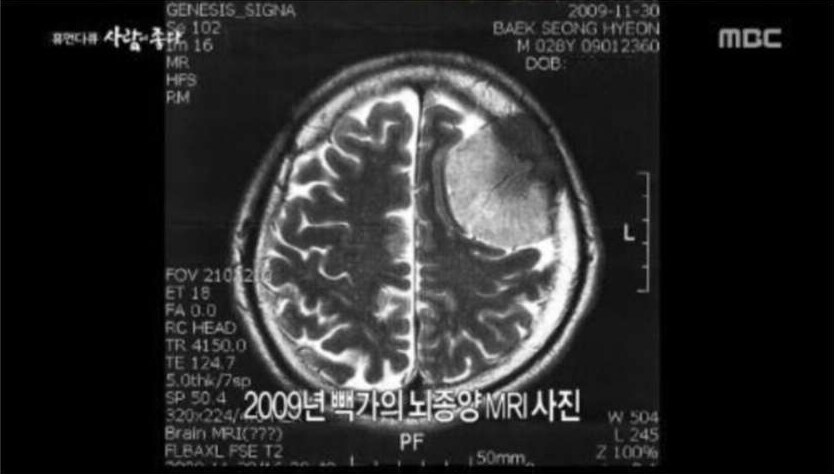

빽가 뇌종양 이겨냈다고는 들었지만 저정도나 절개 한거야????????

테니스공보다 약간 큰 크기의 구체의 종양이었다고 하더라

와씨 뇌종양 앓았다는 것만 알았지 사진으로 보니까 겁나 크네 ㅎㄷㄷㄷㄷ

테니스공보다 약간 큰 크기의 구체의 종양이었다고 하더라 | 25.10.12 14:23 | | |

급성이면 문제가 되는데 천천히 진행되면 뇌가 해당부위의 기능을 나눠갖는다하니까. 그래서 70%가 물로 차있어도 정상인 사람있고